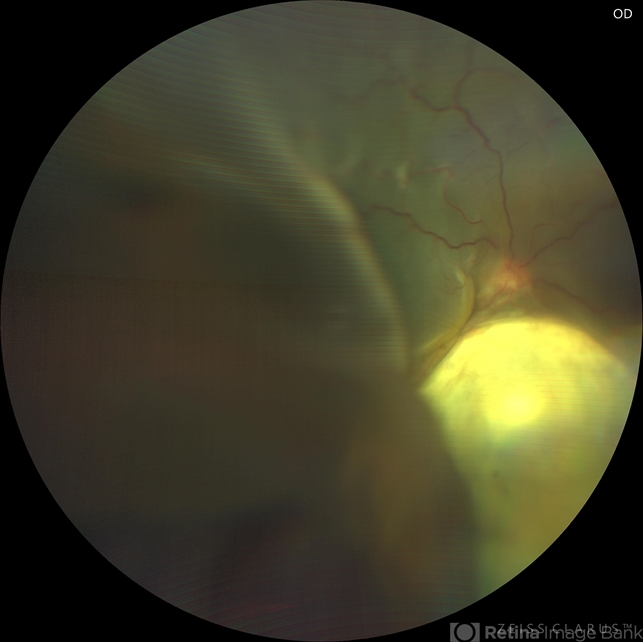

- coloboma of choroid, pre-op

- 17 year-old female with RC coloboma with total bullous retinal detachment